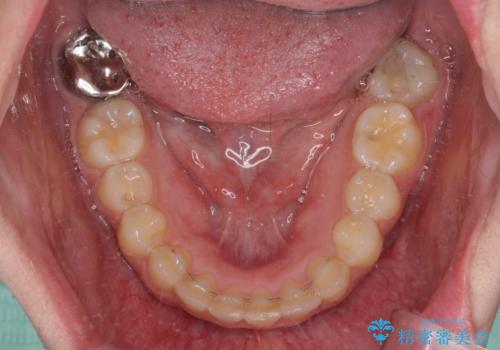

- 前歯のデコボコと八重歯を気にして来院された患者様です。

叢生の程度は中等度であったため、IPR(歯と歯の間を削る)と歯列の側方拡大をメインに、インビザラインを用いて歯列を改善することとしました。

また、下顎骨の右側変位による右側臼歯の咬合を改善させるよう試みることとしました。